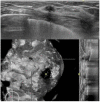

Purpose: The purpose of this study was to prospectively evaluate the interobserver agreement on lesion characterization and the final assessment of automated whole breast ultrasonography (ABUS) images.

Methods: Between March and August 2012, 172 women underwent bilateral ABUS before biopsy guided by handheld ultrasonography (HHUS) and mammography. A total of 206 breast lesions were confirmed histopathologically by biopsy. Three-dimensional volume data from ABUS scans were analyzed by two radiologists without the knowledge of HHUS results or patient clinical information. The two readers described the type, shape, orientation, margin, echogenicity, posterior acoustic features, and categorization of the final assessment of detected breast lesions. Kappa statistics were used to analyze the described characteristics of the breast lesions detected by both of the two readers.

Results: Of the 206 histopathologically confirmed lesions, reader 1 detected 166 lesions and reader 2 detected 150 lesions. A total of 145 lesions were detected by both readers using ABUS images. There was substantial agreement on shape (κ=0.707), and moderate agreement on type, margin, mass orientation, echogenicity, and posterior acoustic features (κ=0.592, 0.438, 0.472, 0.524, and 0.541, respectively). Breast Imaging Reporting and Data System final assessment values yielded a kappa value of 0.3971 when category subdivisions 4A, 4B, and 4C were included. With respect to the C2, C3, C4, and C5 categories, the interobserver agreement was moderate (κ=0.505).

Conclusion: ABUS is a promising diagnostic tool with a good interobserver agreement, comparable to that of HHUS.